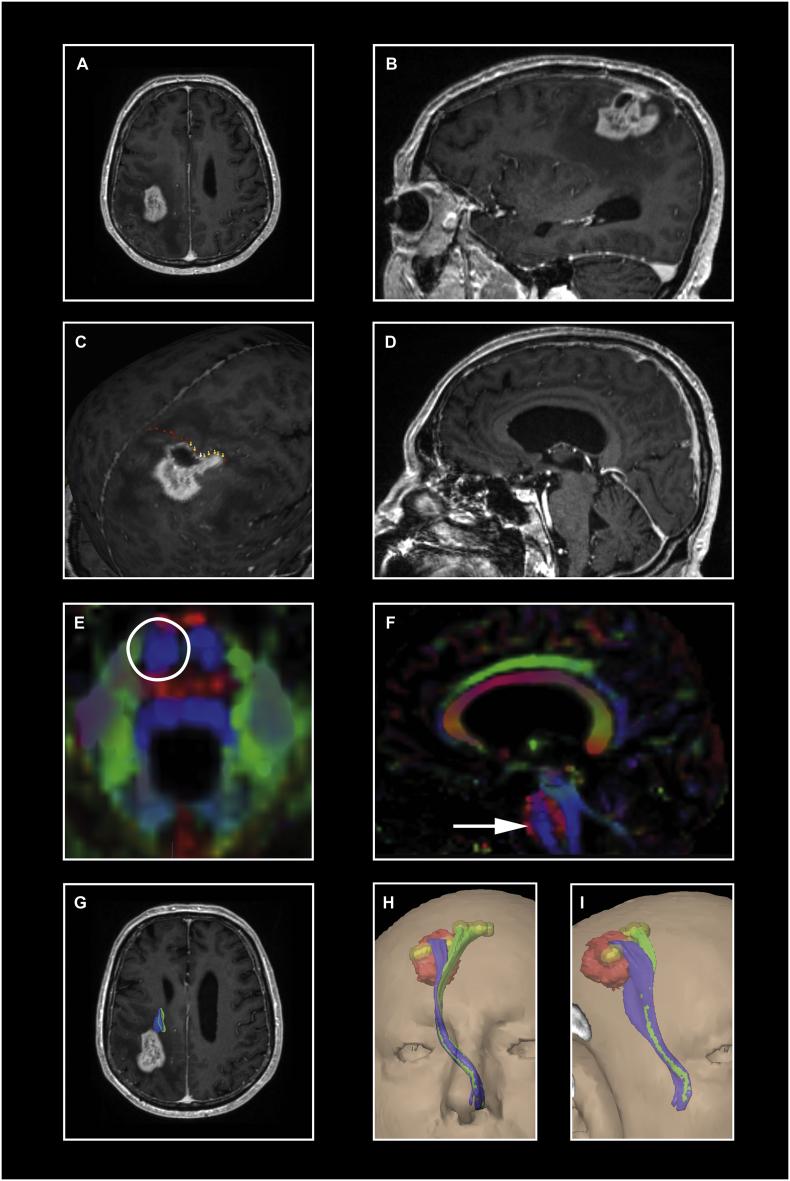

Navigated transcranial magnetic stimulation (nTMS) combined with diffusion tensor imaging (DTI) is used preoperatively in patients with eloquent-located brain lesions and allows analyzing non-invasively the spatial relationship between the tumor and functional areas (e.g. the motor cortex and the corticospinal tract [CST]). In this study, we examined the diffusion parameters FA (fractional anisotropy) and ADC (apparent diffusion coefficient) within the CST in different locations and analyzed their interrater reliability and usefulness for predicting the patients' motor outcome with a precise approach of specific region of interest (ROI) seeding based on the color-coded FA-map.

Prospectively collected data of 30 patients undergoing bihemispheric nTMS mapping followed by nTMS-based DTI fiber tracking prior to surgery of motor eloquent high-grade gliomas were analyzed by 2 experienced and 1 unexperienced examiner. The following data were scrutinized for both hemispheres after tractography based on nTMS-motor positive cortical seeds and a 2nd region of interest in one layer of the caudal pons defined by the color-coded FA-map: the pre- and postoperative motor status (day of discharge und 3 months), the closest distance between the tracts and the tumor (TTD), the fractional anisotropy (FA) and the apparent diffusion coefficient (ADC). The latter as an average within the CST as well as specific values in different locations (peritumoral, mesencephal, pontine).

Lower average FA-values within the affected CST as well as higher average ADC-values are significantly associated with deteriorated postoperative motor function (p = 0.006 and p = 0.026 respectively). Segmental analysis within the CST revealed that the diffusion parameters are especially disturbed on a peritumoral level and that the degree of their impairment correlates with motor deficits (FA p = 0.065, ADC p = 0.007). No significant segmental variation was seen in the healthy hemisphere. The interrater reliability showed perfect agreement for almost all analyzed parameters.

Adding diffusion weighted imaging derived information on the structural integrity of the nTMS-based tractography results improves the predictive power for postoperative motor outcome. Utilizing a second subcortical ROI which is specifically seeded based on the color-coded FA map increases the tracking quality of the CST independently of the examiner's experience. Further prospective studies are needed to validate the nTMS-based prediction of the patient's outcome.

经颅磁刺激导航(nTMS)联合弥散张量成像(DTI)用于语言功能区脑病变患者的术前评估,可无创性分析肿瘤与功能区(如运动皮质和皮质脊髓束 [CST])之间的空间关系。在这项研究中,我们检查了 CST 内不同部位的弥散参数 FA(各向异性分数)和 ADC(表观弥散系数),并分析了它们的观察者间可靠性,以及基于彩色 FA 图进行特定 ROI 种子特异性区域分析对预测患者运动结局的作用。

前瞻性收集了 30 例双侧 nTMS 映射后接受 nTMS 引导下弥散张量纤维追踪术的运动功能区高级别胶质瘤患者的资料,由 2 名有经验的和 1 名无经验的检查者进行分析。在基于 nTMS 运动皮质阳性种子的束追踪后,根据彩色 FA 图定义的第 2 个 ROI(脑桥尾侧 1 层),对双侧数据进行研究:术前和术后运动状态(出院日和 3 个月)、束与肿瘤的最短距离(TTD)、各向异性分数(FA)和表观弥散系数(ADC)。后者作为 CST 内的平均值以及不同部位(瘤周、中脑、脑桥)的特定值。

受影响 CST 内的平均 FA 值较低,以及平均 ADC 值较高与术后运动功能恶化显著相关(p=0.006 和 p=0.026)。CST 内的节段分析显示,弥散参数在瘤周水平上受到特别干扰,其损害程度与运动缺陷相关(FA p=0.065,ADC p=0.007)。健侧半球未见明显节段性变化。几乎所有分析参数的观察者间可靠性均显示出极好的一致性。

在基于 nTMS 的束追踪结果的结构完整性上添加弥散加权成像信息可提高对术后运动结局的预测能力。利用基于彩色 FA 图特异性种子的第二个皮质下 ROI,可提高 CST 的追踪质量,而与检查者的经验无关。需要进一步的前瞻性研究来验证基于 nTMS 的患者预后预测。